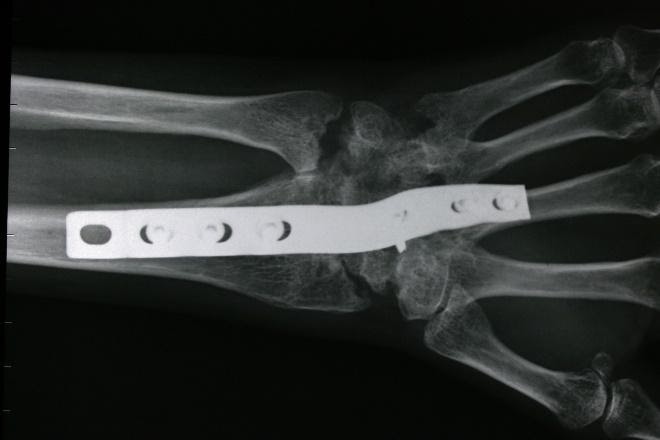

Aşağıda gösterildiği gibi, instabiliteyi sabitlemek için volar ve dorsal ligamanın skafolunatını tendon grefti ile yeniden yapılandırmak genellikle tercih edilen prosedürdür.